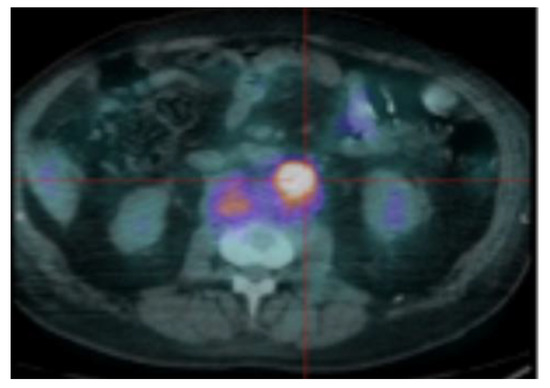

| Interpretation of PET Based on Prognostic Biomarkers | |||

|---|---|---|---|

| Lesions | Definition | Prognostic Biomarker | Reference |

| Focal lesion | Foci of uptake above the surrounding background noise on two successive sections with or without osteolysis on the CT image | Suggested as pejorative prognostic biomarker using cut off 3. | Bartel et al., 2009 [8] |

| Zamagni et al., 2011 [9] | |||

| Abe et al., 2019 [21] | |||

| EMD | Tissue invasion without contiguous bone involvement. | Presence of EMD suggested as pejorative prognostic biomarker | Zamagni et al., 2011 [9] |

| Moreau et al., 2017 [2] | |||

| Moreau et al., 2019 [19] | |||

| PMD | Soft tissue invasion with contiguous bone involvement. | Presence of PMD suggested as pejorative prognostic biomarker | Moreau et al., 2019 [19] |

| Diffuse medullary involvement | Homogenous diffuse uptake of the pelvic-spinal-peripheral skeleton higher than the liver background. | Prognostic value currently not demonstrated | |

| FL SUVmax | Maximal SUVmax of bone focal lesions | Suggested as pejorative prognostic biomarker using cut off of 4.2 | Zamagni et al., 2011 [9] |

| FDG-PET/CT abnormality | Presence of Focal lesion(s) and/or EMD lesion(s) and/or PMD lesion(s) and/or diffuse medullary involvement. | Absence of FDG-PET/CT abnormality considered as a favourable prognostic | Rasche et al., 2017 [16] |

| Abe et al., 2019 [17] | |||